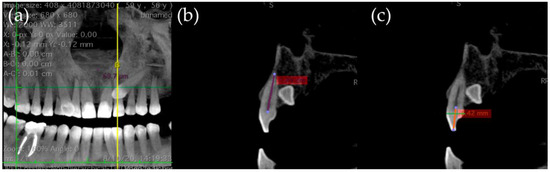

- Mesiodistal diameter on the coronal section of the canine crown (MD3) (Figure 1).

- Occlusogingival (OG3) and buccolingual crown length (BL3) of the canine (Figure 2).

- Length of the lateral incisor´s root (LongRad2), and occlusogingival (OG2) and buccolingual crown length (BL2) (Figure 3).

- Mesiodistal crown diameter of the lateral incisor (MD2) (Figure 4).

- The width across the maxillary arch was measured as follows:

- Transverse distance between the palatal cusps of upper first premolars (1.4 and 2.4 teeth) (Transv4).

- Transverse distance between mesiopalatine cusps of upper first molars (1.6 and 2.6 teeth) (Transv6) (Figure 4).

- The angle formed between the canine´s longitudinal axis and the occlusal plane passing through the cusps of the first molar and premolars (Ang3Poe).

- Angle connecting the canine´s longitudinal axis and the midline, observed in the frontal plane (Ang3LMf).

- Angle among the longitudinal alignment of the canine and the palatal suture, noted in the transverse plane (Ang3LMt).

- Linear measurement of the distance between the canine cusp and the occlusal plane (in millimeters) along the sagittal plane (DCPo) (Figure 5).